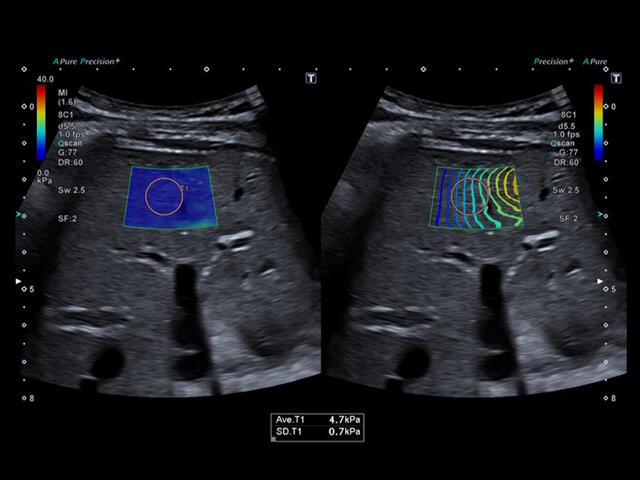

Aplio a550 может работать с линейным матричным датчиком и поддерживает новейшие монокристаллические датчики. Также Aplio a550 поддерживает большое количество дополнительных опций, таких как - SMI, Компрессионная эластография, Эластография сдвижной волны, Smart Fusion, исследования с использованием контраста (CEUS), 3D реконструкции в реальном времени (4D), функции автоматической оценки подвижности миокарда и фракции выброса.

- Эластография сдвиговая (эластометрия): Shear wave

Уровень сосудистой визуализации SMI в сочетании с высокой частотой кадров повышает диагностическую достоверность при оценке поражений, кист и опухолей.

SMI с цветовой кодировкой позволяет одновременно отображать информацию о потоках и оттенках серого с высокой временной и пространственной информацией.